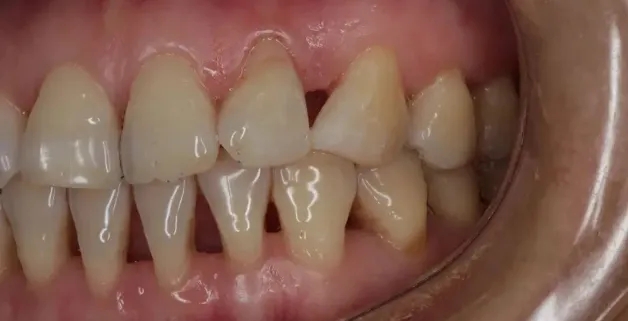

牙周炎,口腔的“沉默杀手”

牙周炎的四大阶段: 第一阶段:牙龈发红,刷牙时有点出血 第二阶段:牙龈开始退缩,牙齿缝显露出来 第三阶段:牙齿会出现松动,时不时有脓液流出来 第四阶段:牙齿脱落